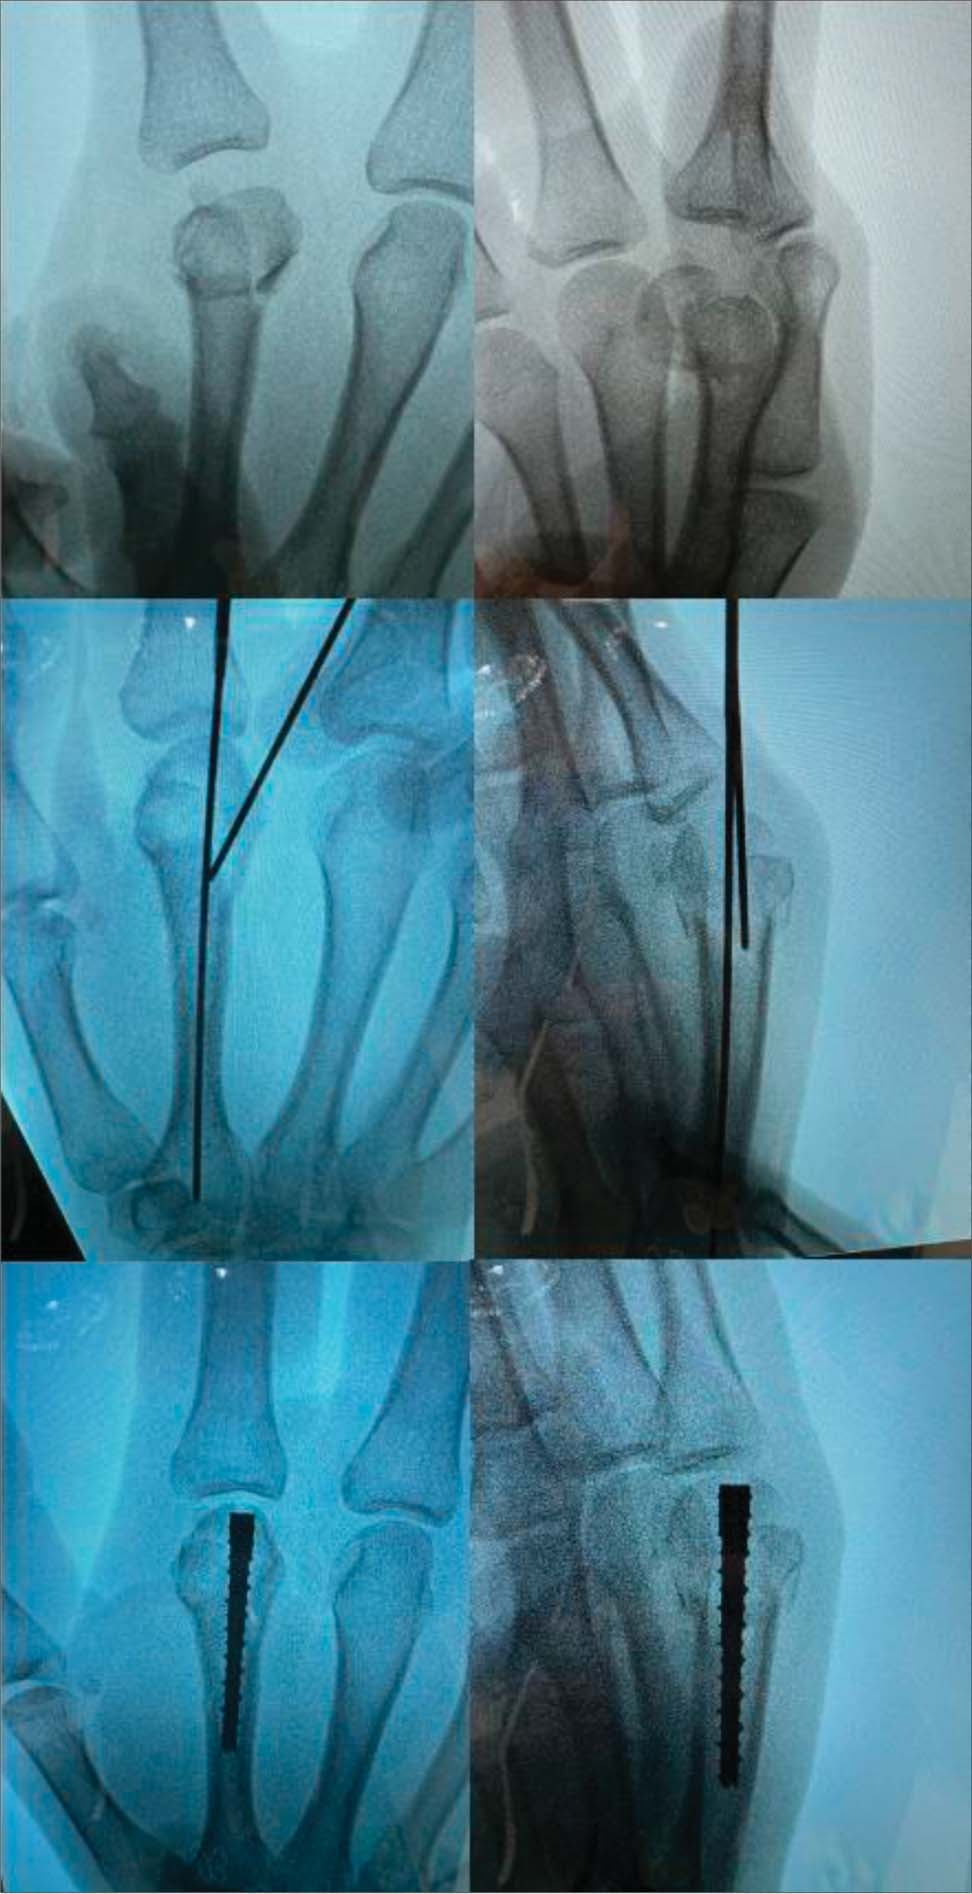

文献表明对于第五掌骨颈骨折没有旋转不良的患者,使用绷带保守治疗是足够的。手术可选择克氏针固定、髓内固定、单独使用骨折段间螺钉、钢板和螺钉等。

其中锁定钢板可立即活动,克氏针组固定至4~6周拔针。掌骨颈骨折重要的手术决策点是有多少骨可用于远端固定。可用于固定的骨量极少的骨折最好采用克氏针固定。

髓内治疗可用于固定的骨量充足的骨折。